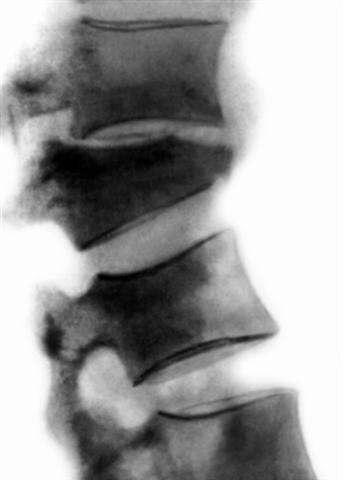

Рис. 10б). Рентгенограмма поясничного отдела позвоночника (боковая проекция) при компрессионном переломе с тяжелой степенью компрессии.